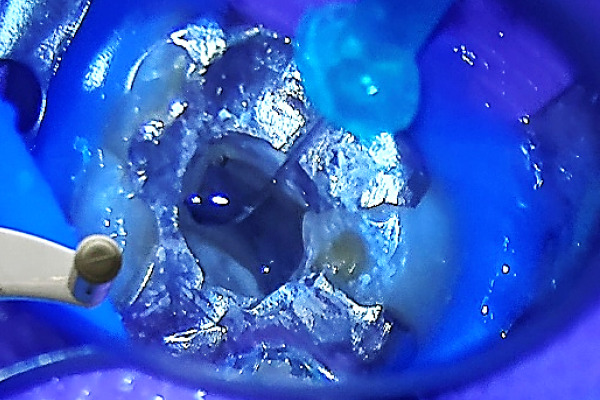

当院のラバーダム

当院は、自費診療と一部保険診療にラバーダムを使用して細菌や唾液の侵入を防ぎます。

歯科治療において、唾液は治療を困難にする「天敵」とされています。

そのため治療環境を無菌状態にし、唾液の影響を最小限に抑えることが治療の成功に直結します。

ですが、ラバーダムを使用することにより治療効果の向上や、口腔内の視野の確保が取れるため安全に治療を行うことができ、詰め物や被せ物の精度を高めることも可能な治療法となります。